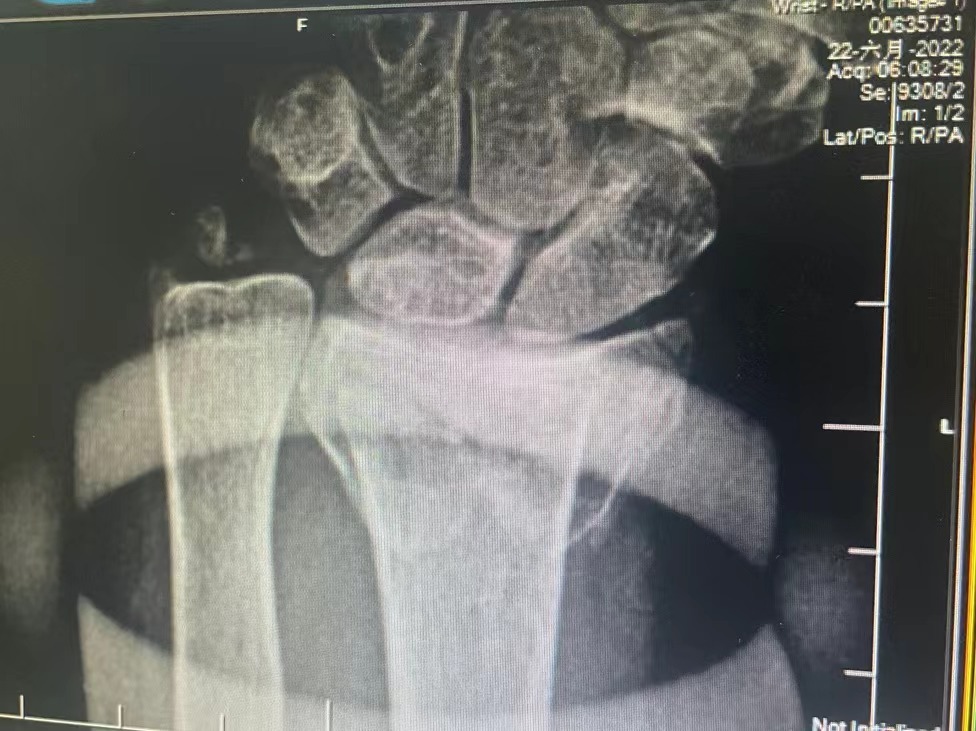

据了解,患者佟阿姨因为家门口的路面有石子,导致老人不小心摔倒,出现腕关节畸形疼痛剧烈,随即拨打了120急救送往医院。接到通知后,外一科主任郎林紧急前往医院救治,仔细询问了患者病史、查体后结合影像表现,诊断为左侧桡骨远端粉碎性骨折伴有尺骨茎突骨折,由于手镯卡在手腕处,无法进行医疗措施,面对这“飞来横祸”,一时间佟阿姨着急的犯了难。在郎林主任的建议下,拨打了119,求助消防队员来取手镯。